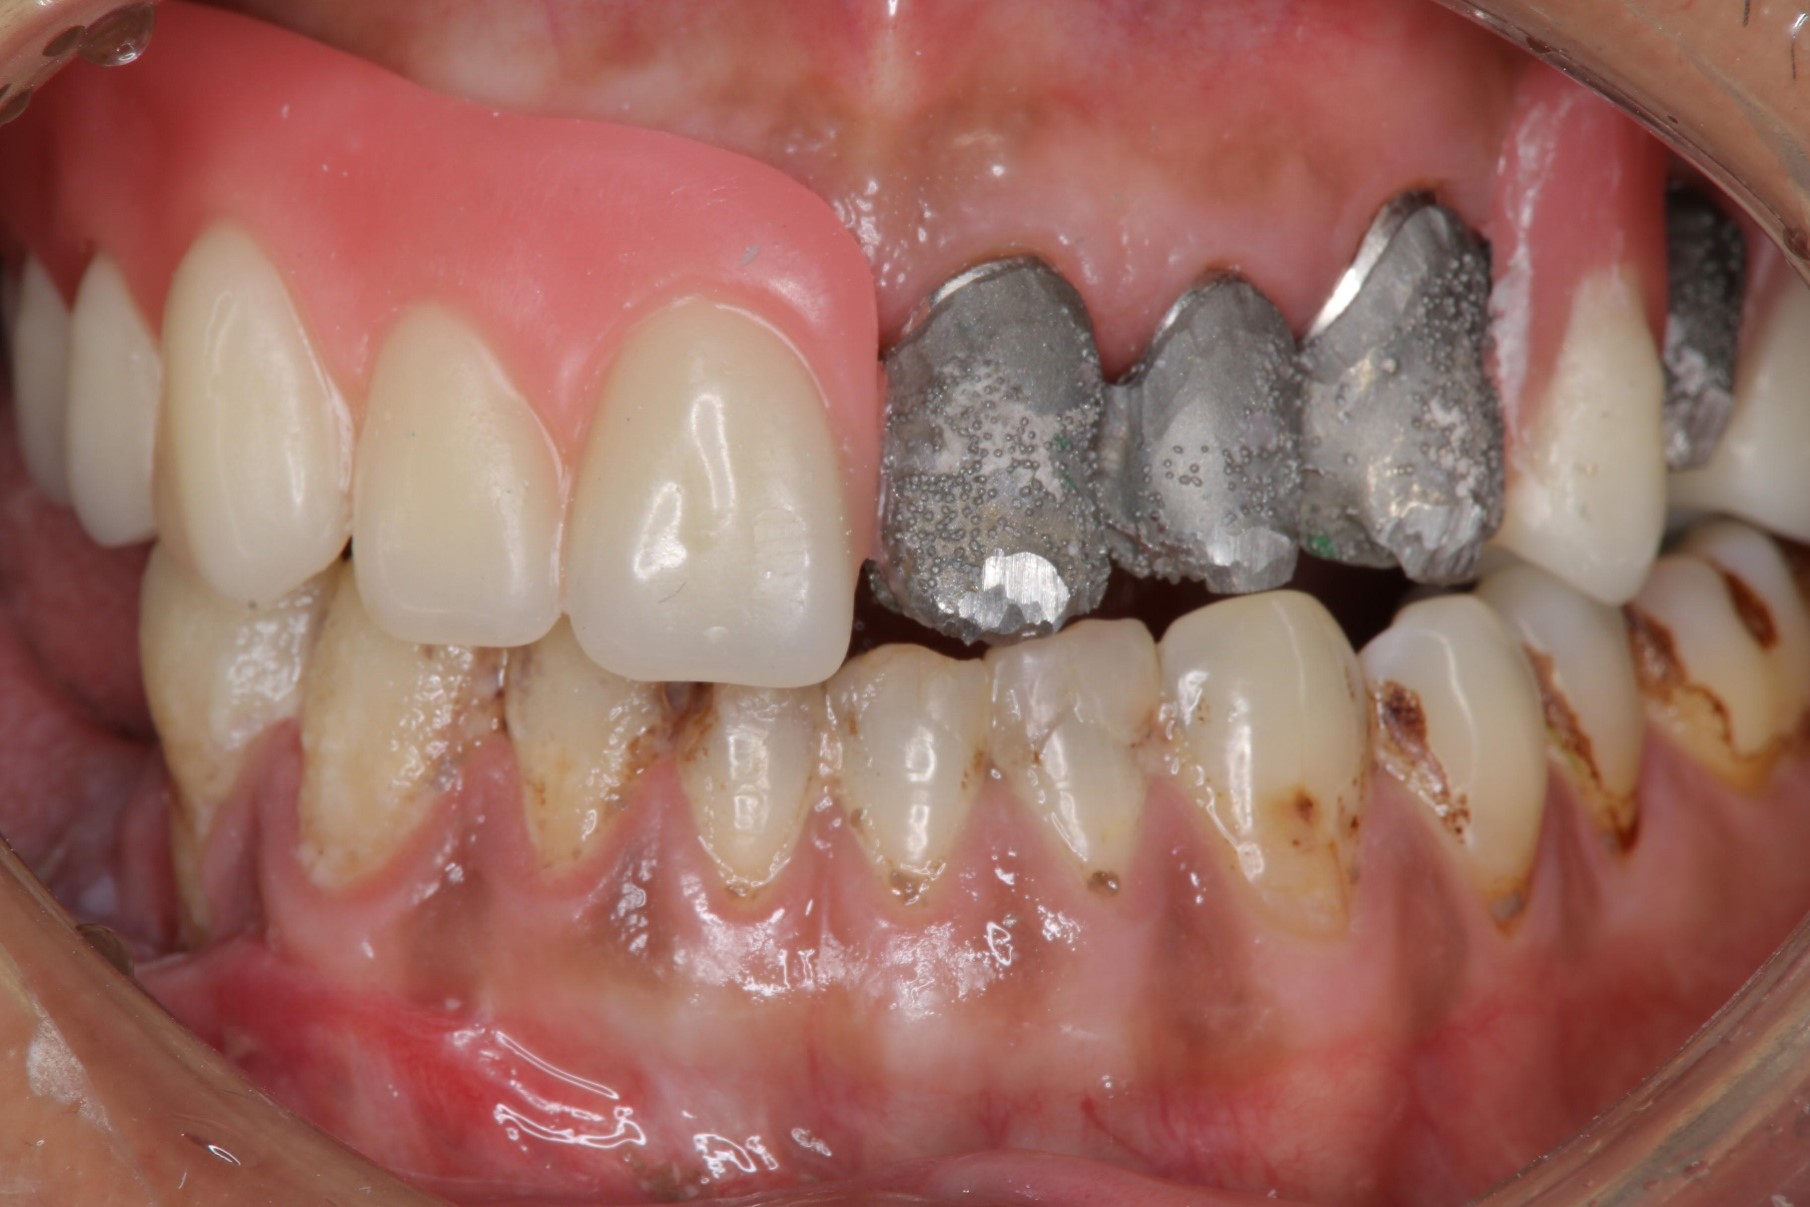

口內試戴

內冠及定位器口內照

覆蓋型活動假牙

活動假牙口內照